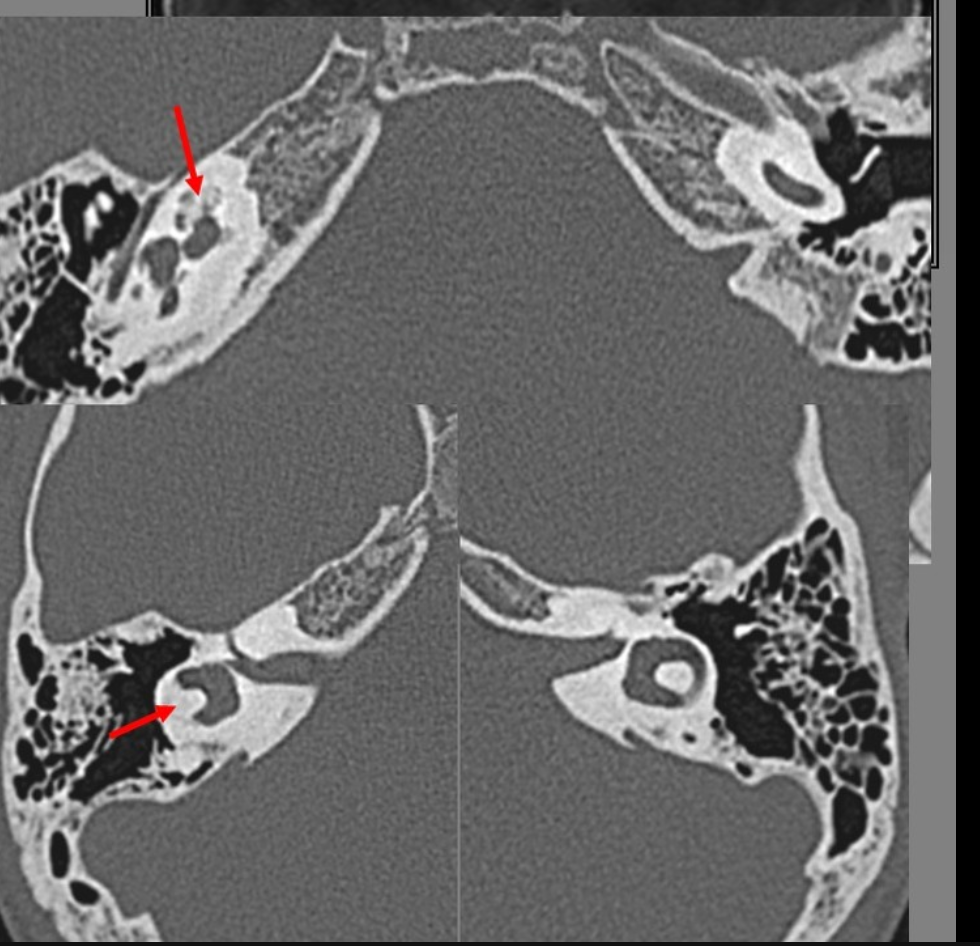

CT

High-density bone deposition within the membranous labyrinth:

mild disease: hazy increase in density within fluid spaces of the membranous labyrinth

moderate disease: focal areas of bony encroachment on fluid spaces of the membranous labyrinth

severe disease: membranous labyrinth completely obliterated by bone replacing fluid spaces

The scala tympani of the basal turn of the cochlea is the most commonly affected site 10.

The term otosclerosis is somewhat of a misnomer. Much of the clinical course is characterised by lucent rather than sclerotic bony changes and hence it is more appropriately known as otospongiosis which is a term preferred by many head and neck radiologists.